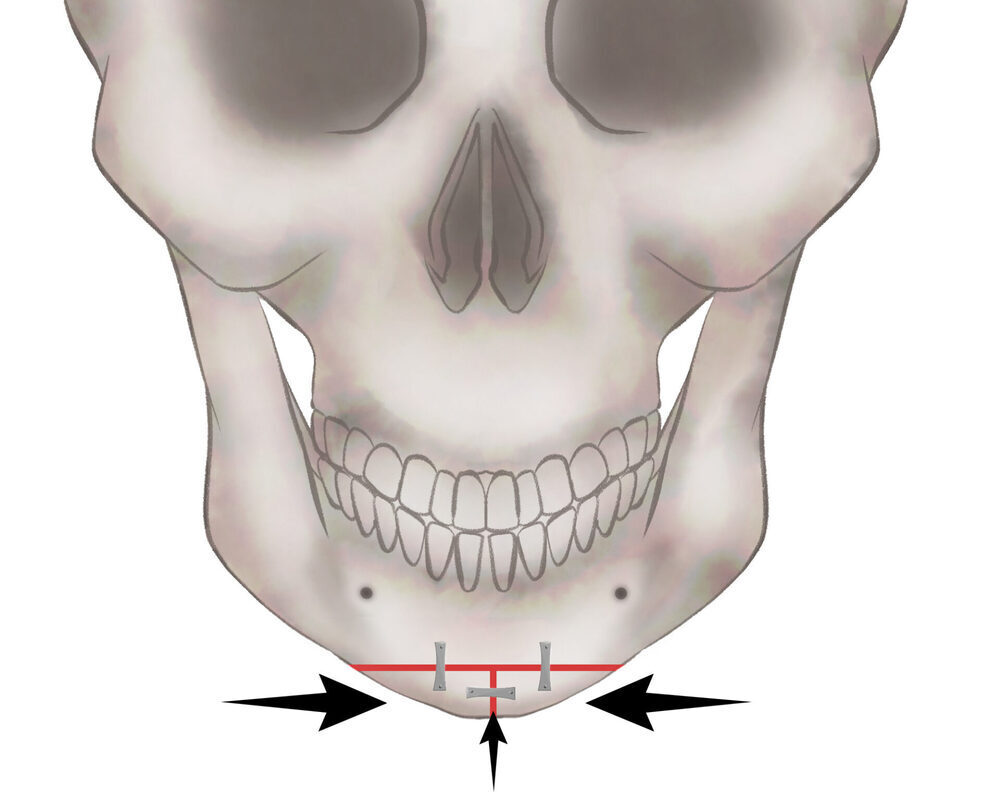

オトガイT字骨切り(Vライン形成)

1.切開線をデザインします

2.骨を切り離す、もしくは取り除きます

3.骨を移動させ段差を削ります

4.プレートで固定します